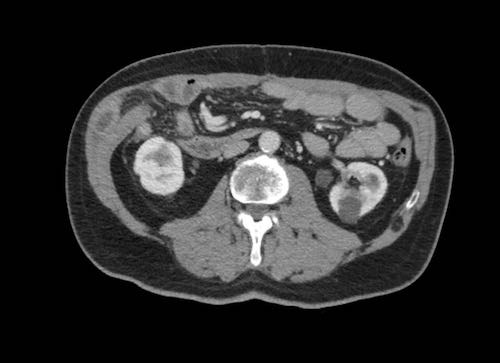

Cuộn xem ảnh CT

Ca lâm sàng 1

Cuộn qua các lát cắt.

Bạn có thể phát hiện tất cả các tổn thương cấy ghép phúc mạc không?

Bệnh nhân này đã được phẫu thuật và toàn bộ phúc mạc được ghi nhận phủ kín bởi các tổn thương u dạng kê.